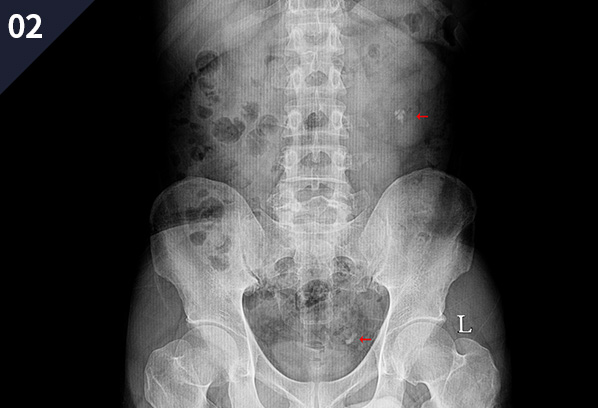

이러한 경우 의심 가능하다!

요 로 결 석 증 상